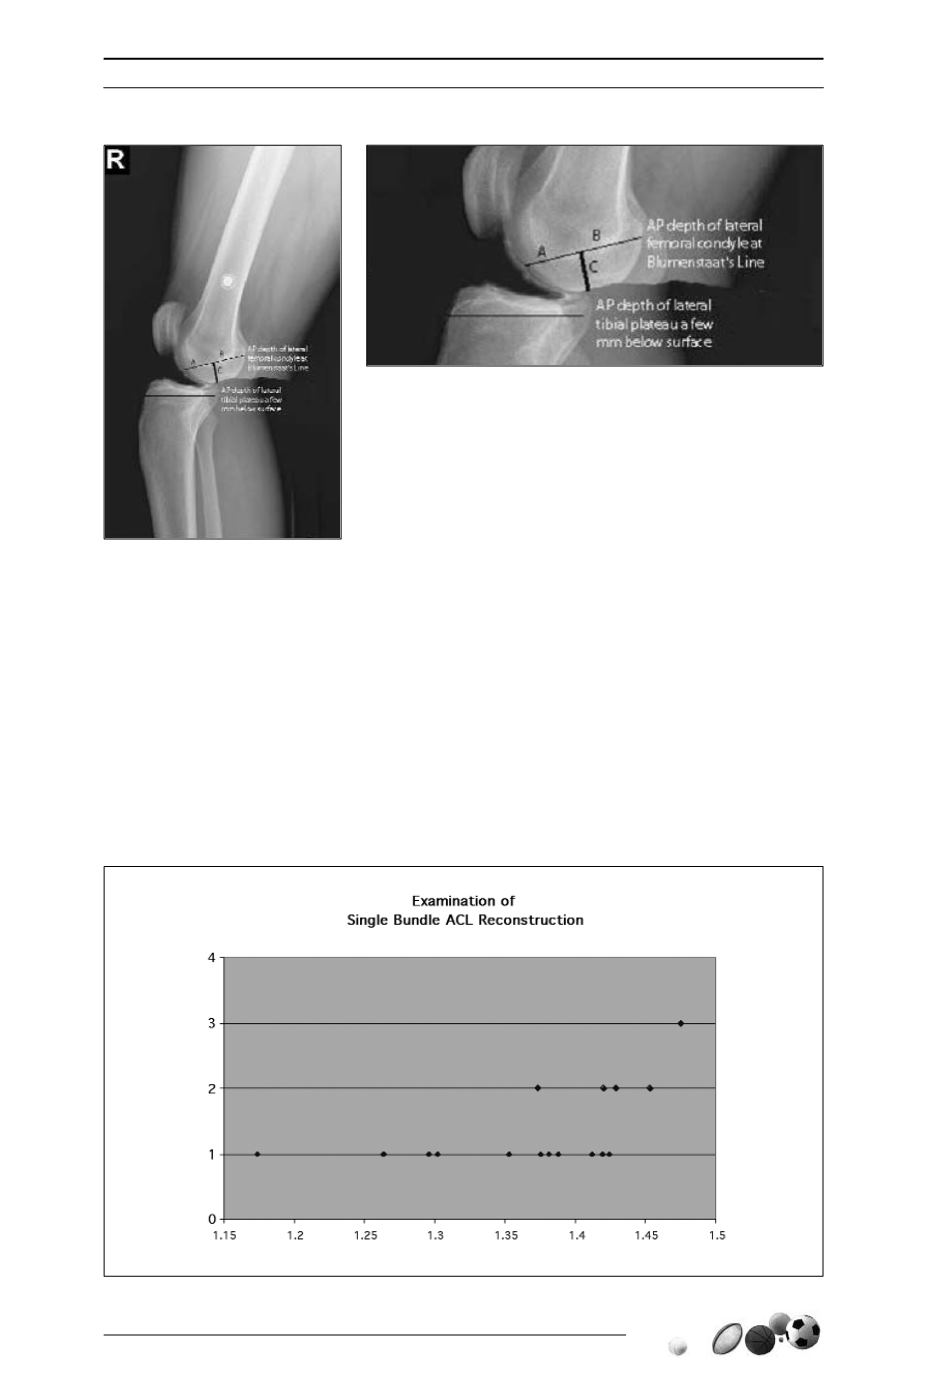

Les dimensions du fémur et du tibia étaient

mesurées sur la radio de profil en appui

monopodal.

On définissait le “Knee Size Ratio” (KSR)

= taille fémorale/taille tibiale, avec :

- Taille fémorale (condyle externe) = A + B + C

- Taille tibiale = distance antéro-postérieure

au niveau sous-chondral.

On définissait le fémoro-tibial Mismatch

quand KSR (Knee Size Ratio) > 1.4

On retrouvait une corrélation entre le grade

du pivot shift et le “Knee Size Ratio”.

Grade du Pivot Shift

Pivot Grade